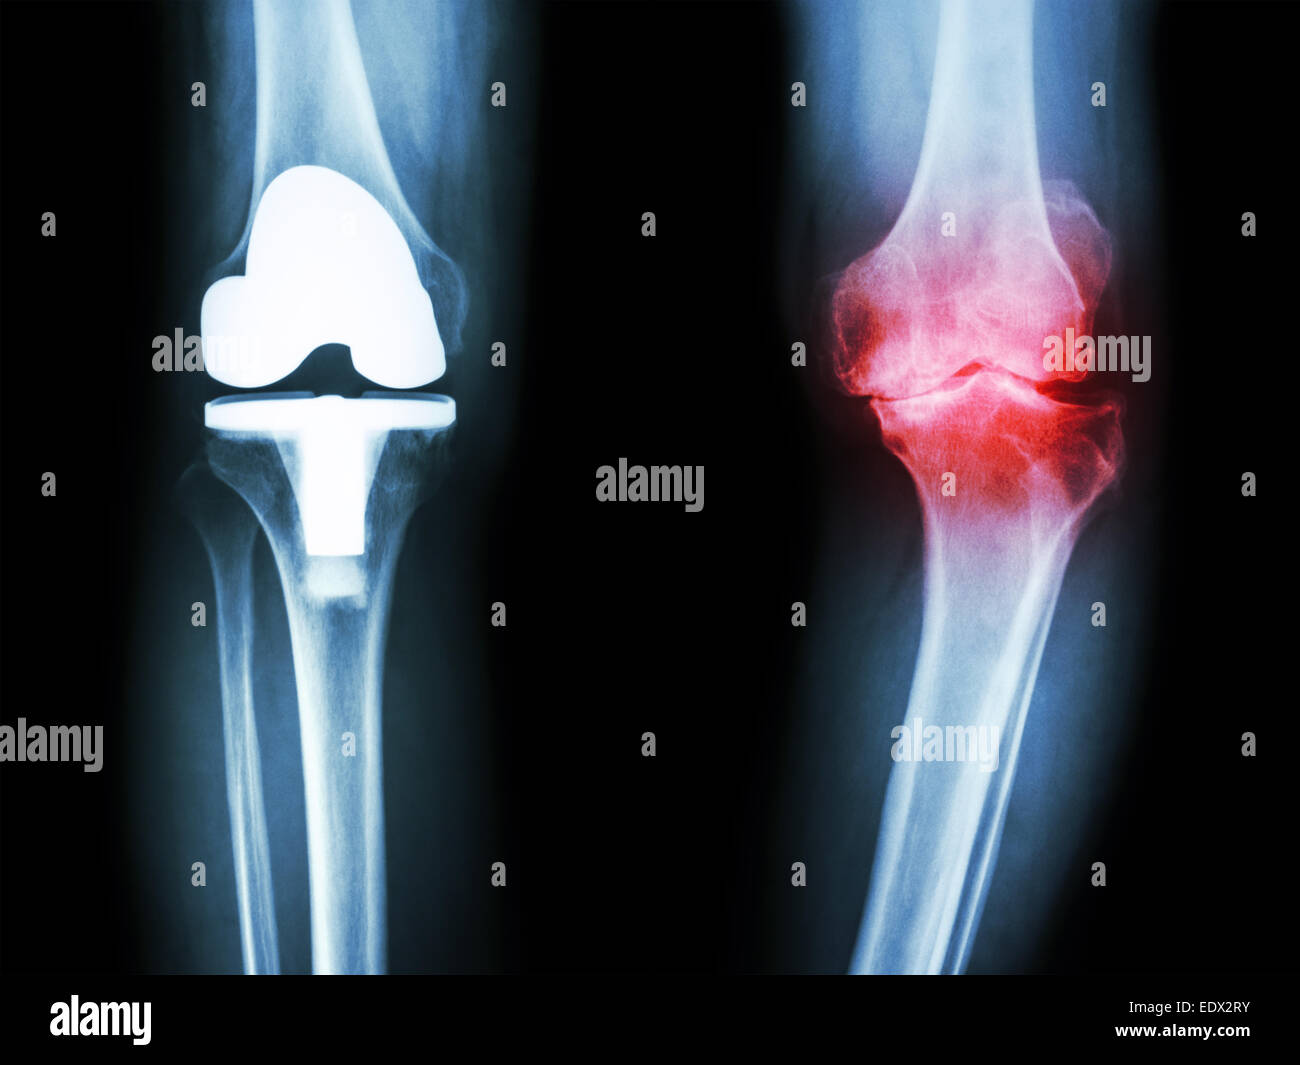

Film x-ray de l'arthrose du genou genou articulation artificielle et patient Banque D'Imageshttps://www.alamyimages.fr/image-license-details/?v=1https://www.alamyimages.fr/photo-image-film-x-ray-de-l-arthrose-du-genou-genou-articulation-artificielle-et-patient-77404991.html

Film x-ray de l'arthrose du genou genou articulation artificielle et patient Banque D'Imageshttps://www.alamyimages.fr/image-license-details/?v=1https://www.alamyimages.fr/photo-image-film-x-ray-de-l-arthrose-du-genou-genou-articulation-artificielle-et-patient-77404991.htmlRFEDX2RY–Film x-ray de l'arthrose du genou genou articulation artificielle et patient

Film x-ray de l'arthrose du genou genou articulation artificielle et patient Banque D'Imageshttps://www.alamyimages.fr/image-license-details/?v=1https://www.alamyimages.fr/photo-image-film-x-ray-de-l-arthrose-du-genou-genou-articulation-artificielle-et-patient-77404992.html

Film x-ray de l'arthrose du genou genou articulation artificielle et patient Banque D'Imageshttps://www.alamyimages.fr/image-license-details/?v=1https://www.alamyimages.fr/photo-image-film-x-ray-de-l-arthrose-du-genou-genou-articulation-artificielle-et-patient-77404992.htmlRFEDX2T0–Film x-ray de l'arthrose du genou genou articulation artificielle et patient